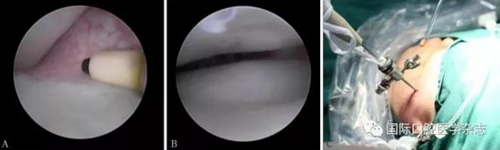

(1)顳下頜關(guān)節(jié)鏡微創(chuàng)治療。使用關(guān)節(jié)鏡治療的適應(yīng)證:顳下頜關(guān)節(jié)紊亂病,保守治療效果不佳,病情較重者(圖17)。2)顳下頜關(guān)節(jié)盤復(fù)位錨固術(shù)(圖18)。使用顳下頜關(guān)節(jié)盤復(fù)位錨固術(shù)治療的適應(yīng)證:顳下頜關(guān)節(jié)紊亂病,保守治療無效,關(guān)節(jié)鏡手術(shù)效果不佳者。

A:射頻刀松解黏連帶;B:復(fù)位后的關(guān)節(jié)盤;C:關(guān)節(jié)鏡術(shù)中。

圖 17 關(guān)節(jié)鏡手術(shù)